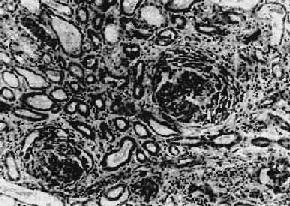

图12-10 弥漫性系膜增生性肾小球肾炎 肾小球系膜区略增宽,系膜细胞数量增多

二、弥漫性系膜增生性肾小球肾炎弥漫性系膜增生性肾不球肾炎(diffuse mesangial proliferative glomerulonephritis)的病变特点为弥漫性肾小球系膜增生。多见于青少年,我国及东方国家比西方国家多见。本病可为原发性,也可在一些全身性疾病时发生,如系统性红斑狼疮、过敏性紫癜等。有些迁延性毛细血管内增生性肾小球肾炎病变持续不退,可表现为系膜增生性肾小球肾炎。临床可表现为肉眼或镜下血尿或蛋白尿,或两者兼有。少数表现为肾病综合征。 【病理变化】 主要病变为肾小球系膜细胞和基质增生,系膜区增宽(图12-10,图12-11)。毛细血管壁无明显变化,管腔通畅。系膜内可有少数单核细胞和中性粒细胞浸润。病变严重者可引起系膜硬化。